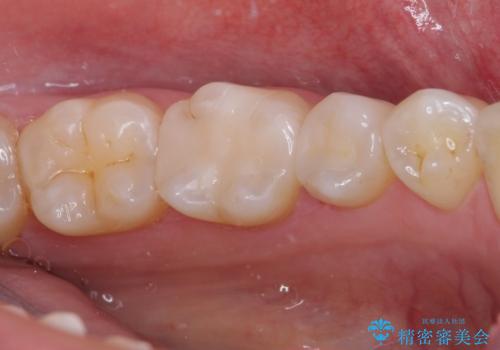

銀歯をセラミックにしたい セラミックインレー修復

- 銀歯をセラミックにしたいとのことで来院された患者様です。

自然な色調で大変満足されました。